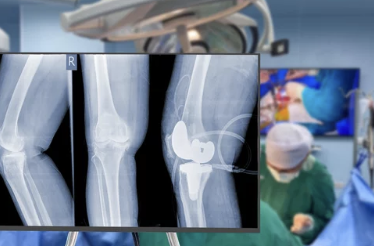

✅ 인공관절 치환술 (말기 관절염의 경우)

- 무릎 관절이 심하게 손상된 경우 인공관절로 대체

- 주로 60대 이상 고령 환자에게 시행